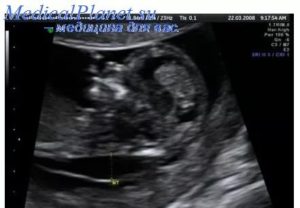

Стоит знать! Легче всего на УЗИ обнаружить образования, имеющие более крупные размеры.

- Истинные кисты пуповины. Они появляются из оставшихся частей аллантоисного протока (в некоторых случаях из остатков желточного). Во время проведения ультразвукового исследования, они имеют анэхогенное содержимое. При этом истинные образования могут иметь размер от полсантиметра и в некоторых случаях достигают размеров в 10 см. Зачастую они развиваются в непосредственной близости от самого тела плода. Однако проведение дифференцированного УЗИ является возможным не всегда.

- Проведение УЗИ плаценты, а также плода, для определения локализации, аномалии и её параметров;